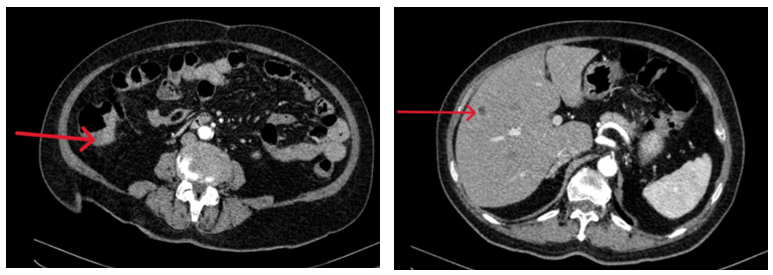

- Chụp CT ổ bụng có tiêm thuốc: Đại tràng lên thành dày 20mm, ngấm thuốc sau tiêm. Kích thước bình thường, bờ đều. Nhu mô gan phải có vài nốt giảm tỷ trọng 5mm ngấm thuốc kém sau tiêm

Hình 3: Chụp CT ổ bụng có hình ảnh dày thành đại tràng lên (bên trái) và nốt ngấm thuốc kém ở nhu mô gan (bên phải)

- Chụp MRI ổ bụng có tiêm thuốc đối quang từ: Gan kích thước bình thường, bờ đều. Nhu mô gan có vài nang đường kính 5mm, không thấy bất thường cấu trúc và tín hiệu.

Hình 4: Chụp MRI ổ bụng có hình ảnh nang gan (mũi tên)